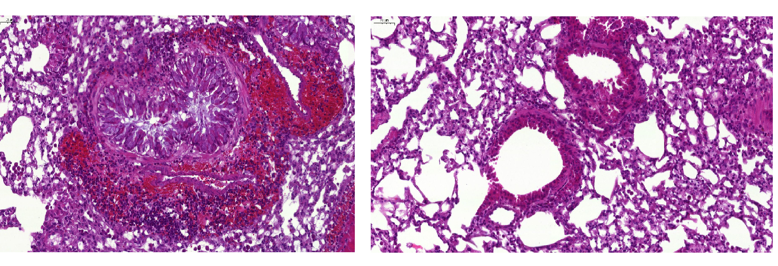

Un effet important sur les symptômes de l’asthme a également été observé : chez les animaux étudiés, la vaccination a été associée à une diminution des taux d’IgE et de l’éosinophilie ainsi qu’à une réduction de production de mucus et de l’hyperréactivité des voies respiratoires.